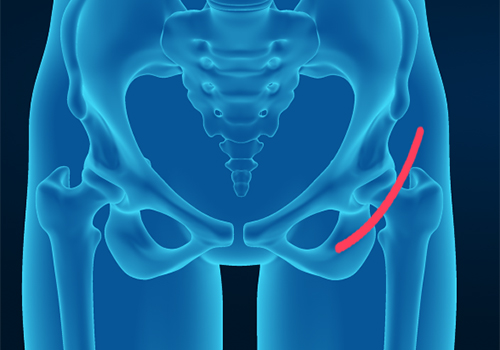

Hip fractures involve a break that occurs near the hip in the upper part of the femur or thigh bone. The thigh bone has two bony processes on the upper part - the greater and lesser trochanters. The lesser trochanter projects from the base of the femoral neck on the back of the thigh bone.

Hip trauma is an injury in the hip due to the impact caused by incidents such as a car accident or a hard fall. The injury can be a bone break or dislocation or both.